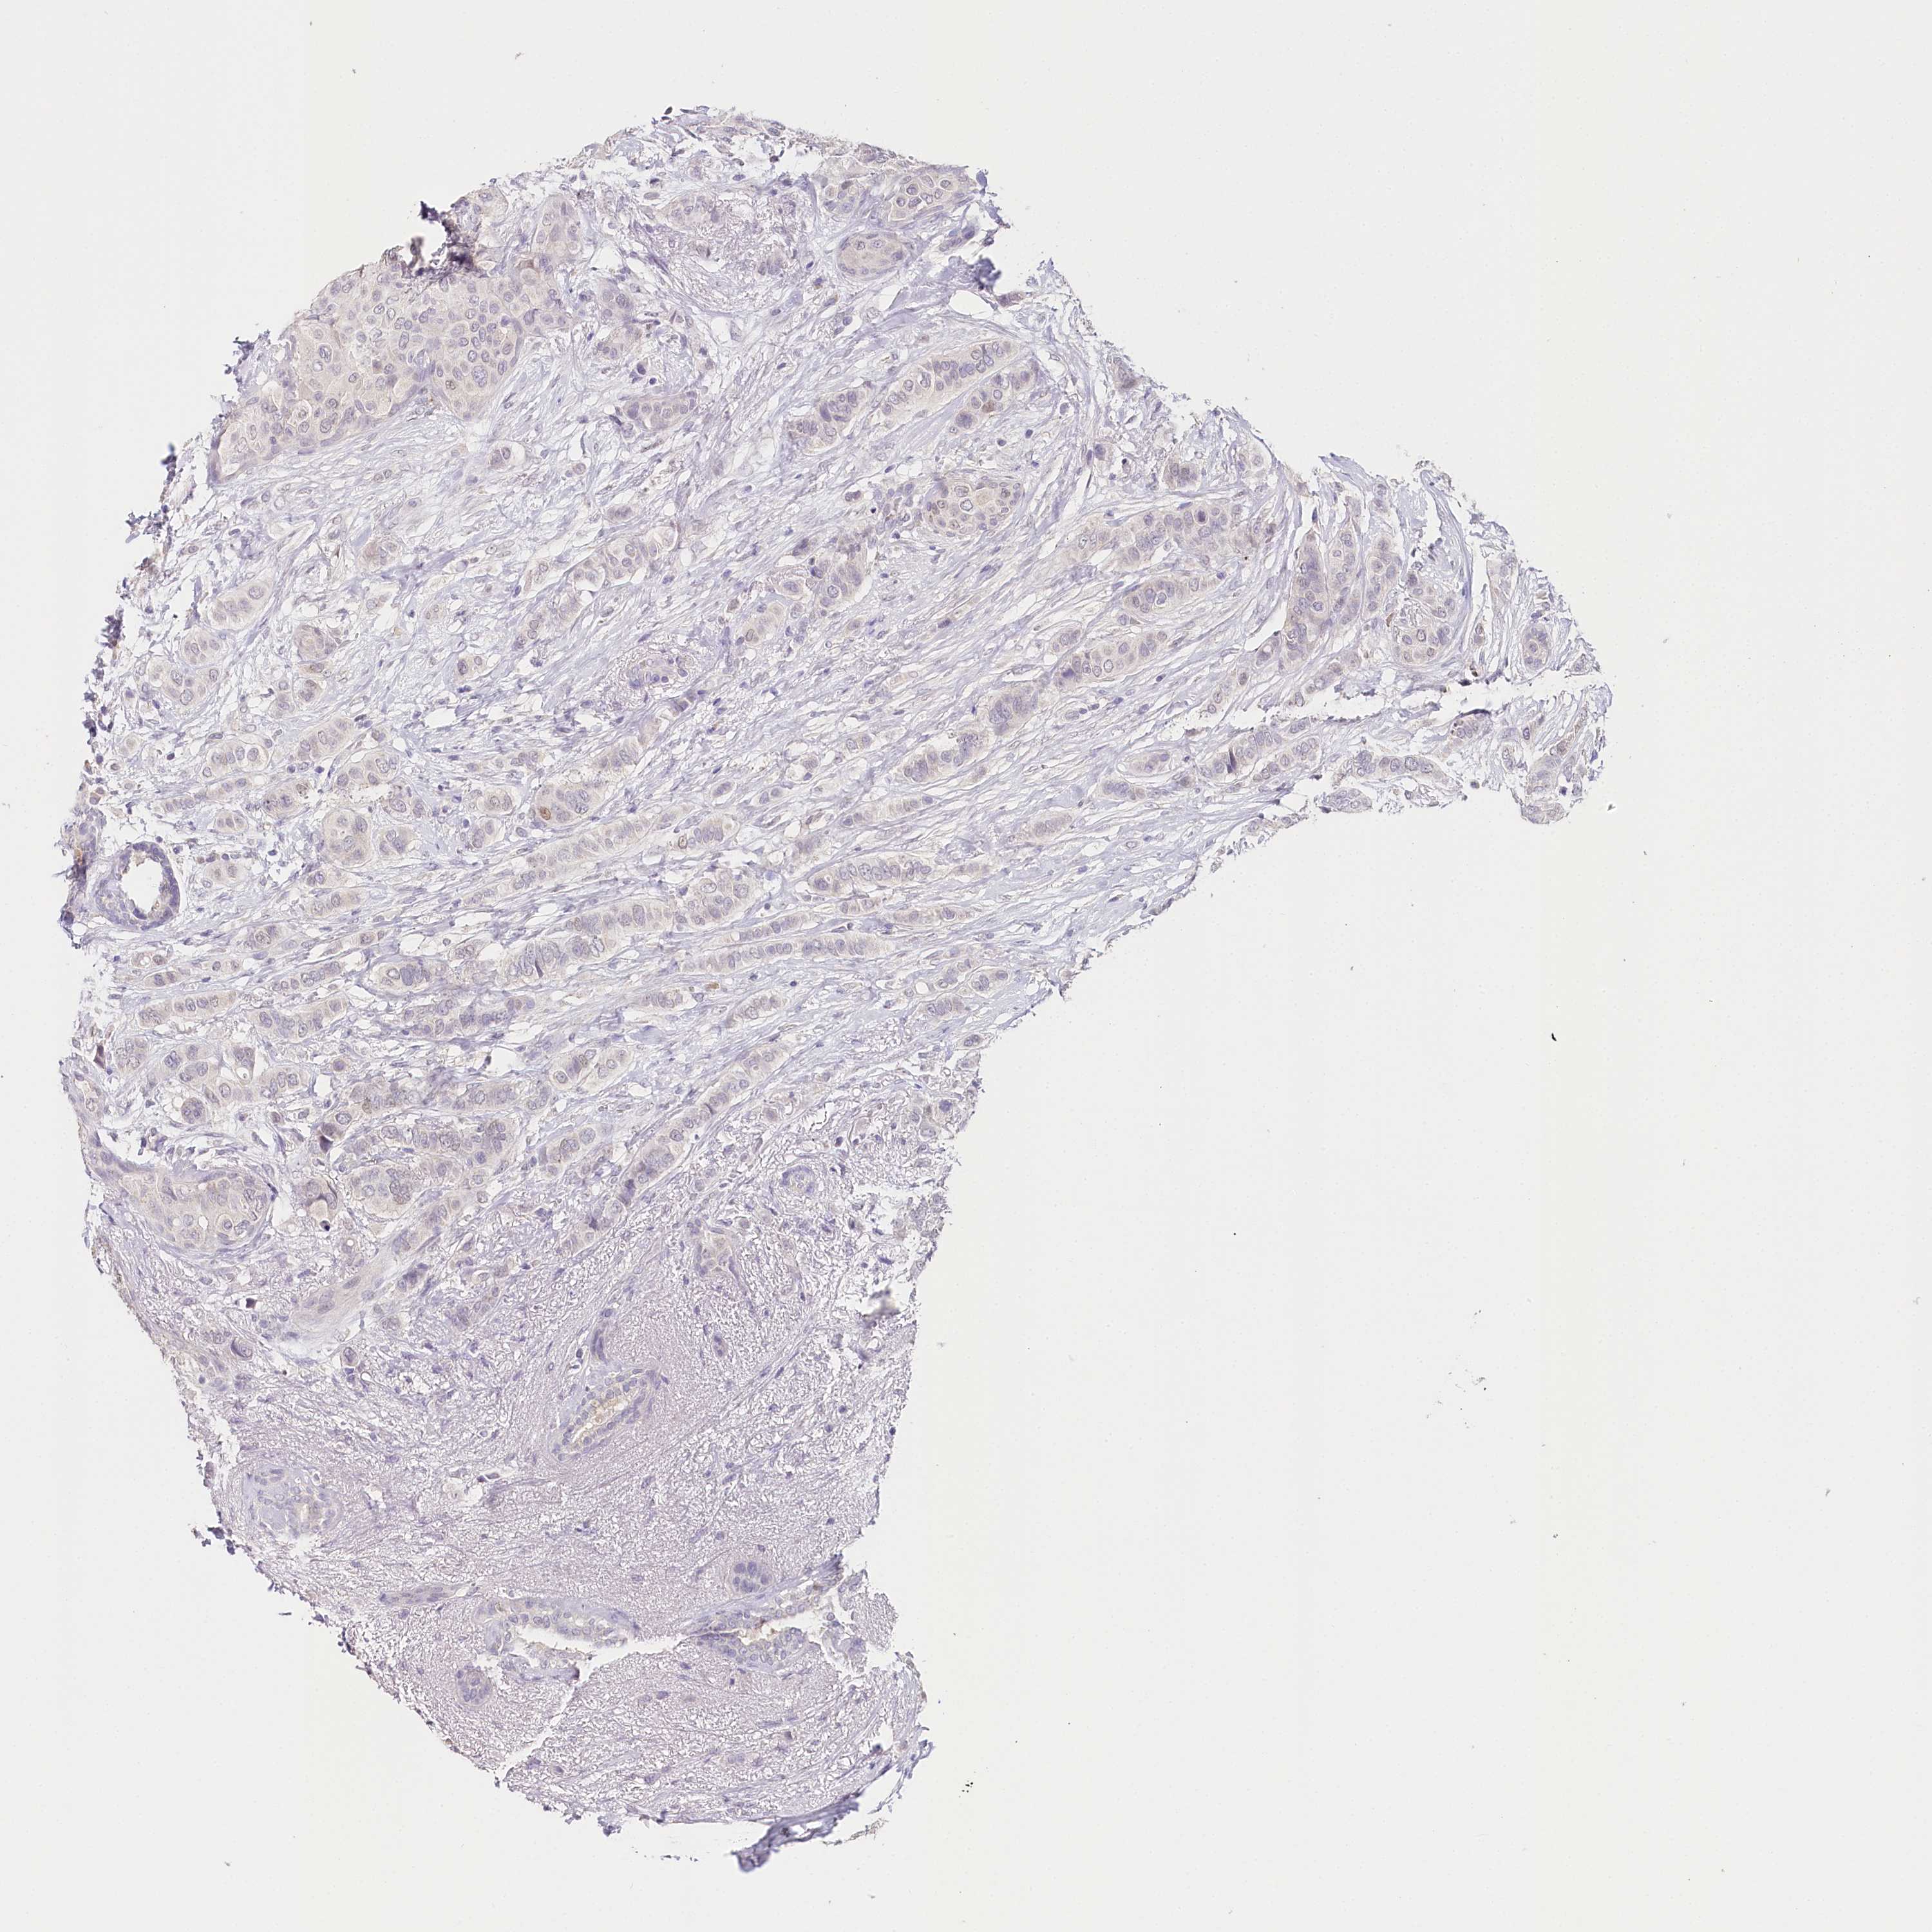

BRCA TCGA BRCA VALIDATION PROTEIN EXPRESSION

ANTIBODIES

AND

VALIDATION